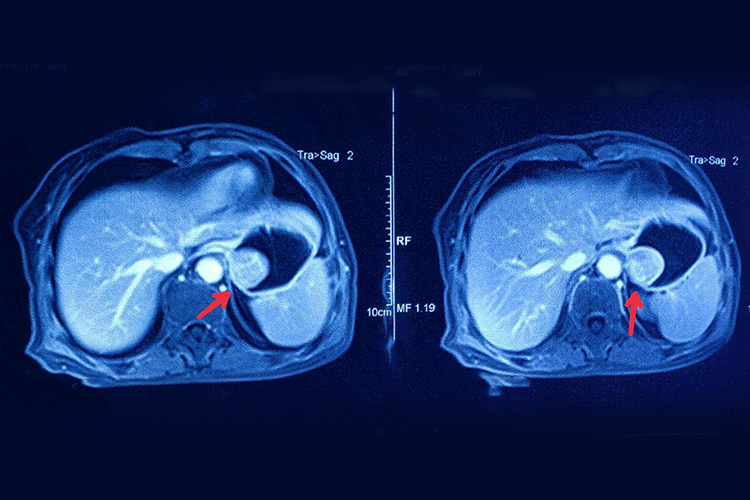

胃外面长肿瘤表现为影像学检查可见胃外壁长瘤体,常见症状为胃出血。

胃外面长肿瘤可能是胃平滑肌瘤、胃脂肪瘤等,均可通过外科手术切除治疗。